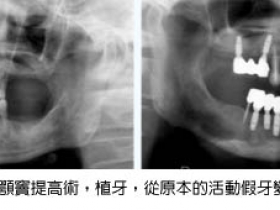

20100827植牙全口重建~龍霖醫師

2010-08-27